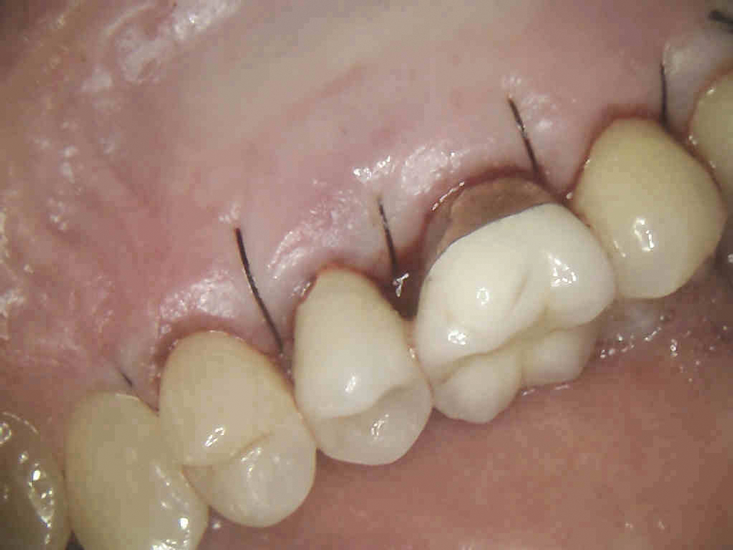

(6.) Immediate postoperative view after the flap was sutured into place (Photography courtesy of Stephen Fucini, DMD).

Figure 6

After TCA treatment, the resorptive cavity should be restored with a biocompatible restorative material that does not wash out in saliva or gingival crevicular fluid. Due to this latter requirement, resin-modified glass ionomers are often more appropriate restorative materials in these cases than other bioceramic materials.8,9 Once restored, the patient should be recalled for follow-up appointments at 6 months and at 1 year postoperatively, at a minimum, to assess the progress of healing and for any recurrent resorption.5